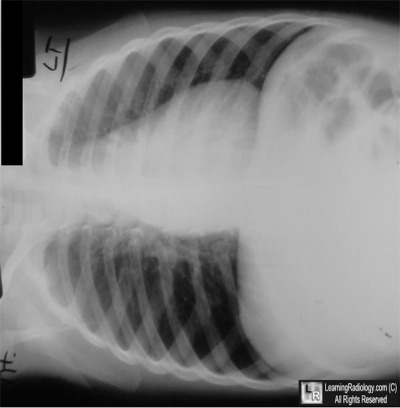

Additional Images-Right Lateral Decubitus Chest Radiograph

Right Lateral Decubitus Chest Radiograph

3. Aspirated foreign body

Aspirated foreign body

- Children between 1-3 are most at risk

- Twice as common in males as females

- Up until age 15, both right and left main bronchi arise at about the same angle from the trachea so that objects may be aspirated into either side

- Afterwards, the right main bronchus arises in a less acute, more straight path than the left